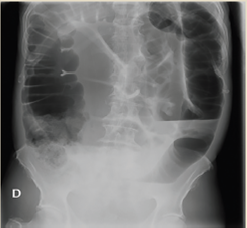

Paciente del sexo masculino, de 76 años, quien inició padecimiento actual hace 72 horas, con presencia de distensión y dolor abdominal opresivo 8/10 por “escala visual análoga” detonado por ingesta, sin presentar evacuaciones ni canalización de gases. Refirió tratamiento sintomático con antiespasmódicos, antiácidos y medicación local transrectal (supositorio), sin mejoría. Como antecedentes relevantes menciona patrón intestinal anormal con tendencia a la constipación crónica. A la exploración física dirigida, abdomen prominente a expensas de distensión de asas intestinales, peristaltismo disminuido con ruidos hidroaéreos, timpánico a la percusión con características metálicas, doloroso a la palpación superficial y media, con hiperalgesia e hiperbaralgesia, signo de rebote dudoso, tacto rectal con ámpula rectal vacía. Se realizaron radiografías posteroanterior de tórax y anteroposterior de abdomen identificando colon sigmoides redundante con aumento del patrón de distribución aérea, la cual ocasionó sobreposición de asas sobre el ángulo hepático y esplénico, presencia de material de residuo en íleon y colon ascendente, así como edema interesa (figura 1 y 2).

Figura 2 AP de abdomen. Colon sigmoides redundante, gran aumento del patrón de distribución aérea, sobreposición de asas sobre marco colónico, ángulo hepático y esplénico, imagen en grano de café